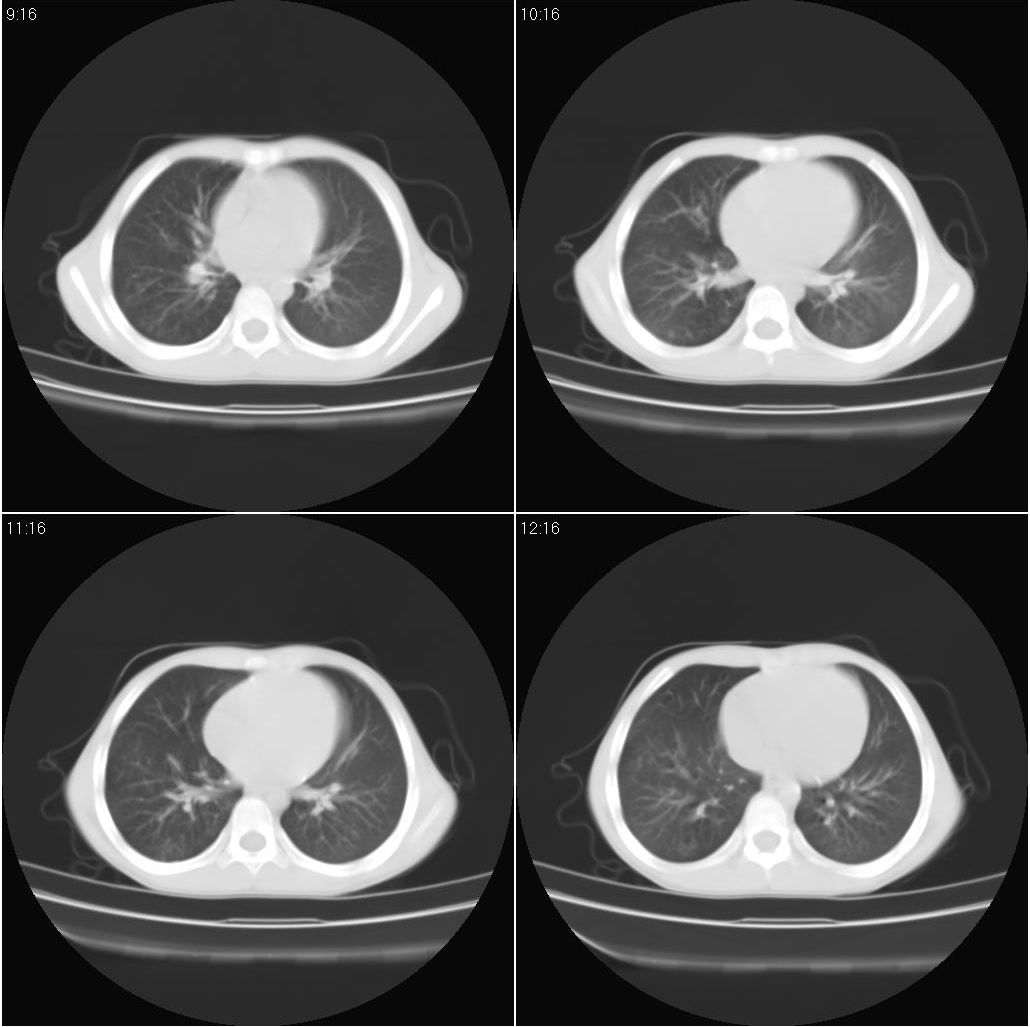

男,7岁。两周前发烧,平片检查提示肺炎。用抗生素治疗烧退,但病变仍没有消退。到防疫站进行结核的ppd试验检查为阴性。

9月20号ct检查情况: